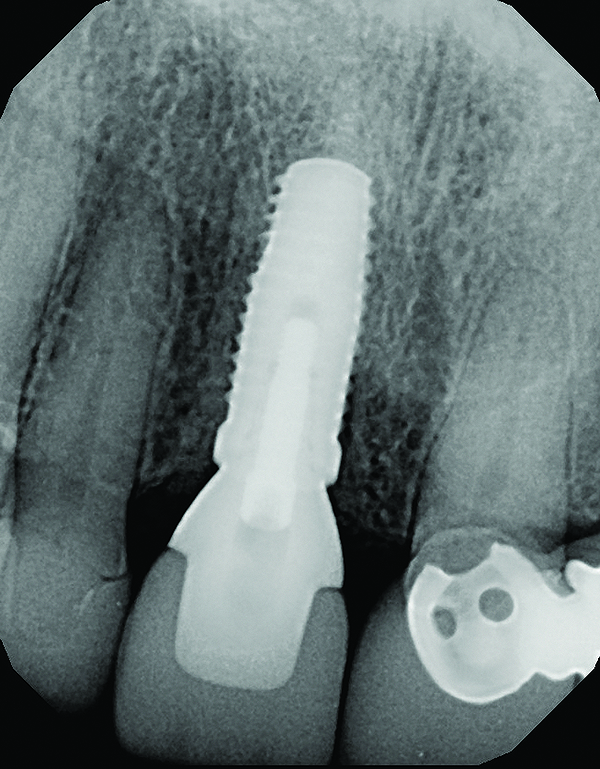

Fig 18. Radiograph taken immediately after placement of the definitive crown confirmed complete removal of all the cement.

Figure 18